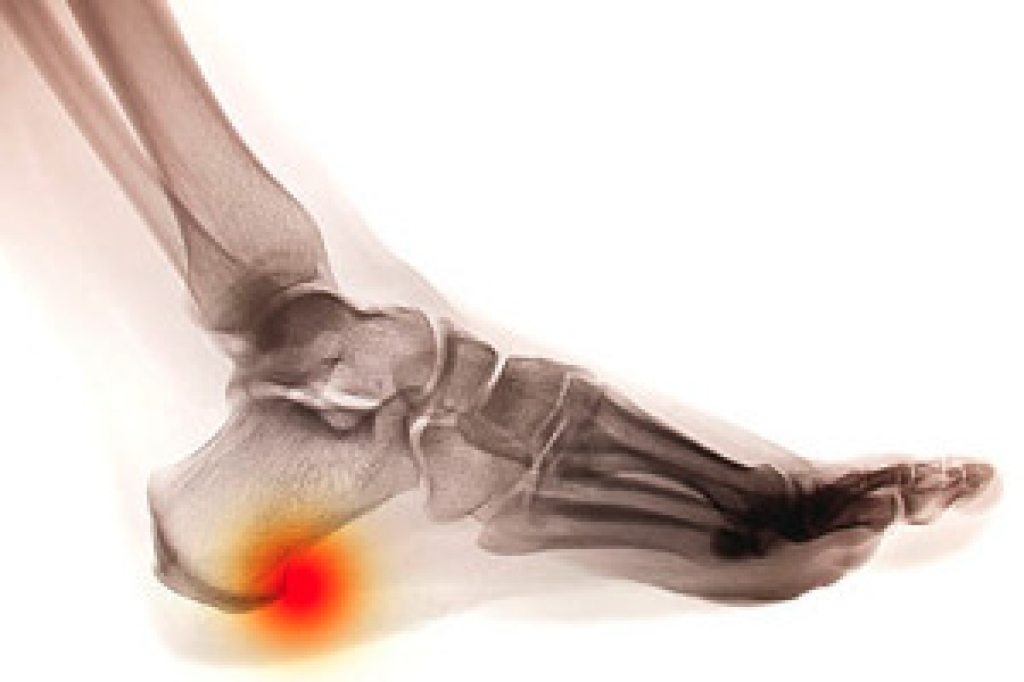

Heel pain can occur in different areas, and identifying the exact location often helps determine the cause. Pain beneath the heel is frequently linked to plantar fasciitis, which occurs when the band of tissue running along the sole becomes strained and inflamed. Pain felt at the back of the heel may be related to Achilles tendonitis, where the tendon attaching the calf muscles to the heel becomes irritated. Discomfort on the sides of the heel may stem from bursitis, an inflammation of fluid-filled sacs that cushion the heel. In some cases, pain deep within the heel may point to a stress fracture, often caused by repetitive impact activities, like running. Risk factors include wearing shoes that lack adequate support, long hours of standing, high-impact exercise, and foot shapes such as flat feet or high arches. A podiatrist can determine the source of your heel pain and provide effective treatment. If you are experiencing heel pain, it is suggested that you make an appointment with a podiatrist for an exam, diagnosis, and treatment.

Heel pain is often associated with plantar fasciitis. The plantar fascia is a band of tissues that extends along the bottom of the foot. A rip or tear in this ligament can cause inflammation of the tissue.

Achilles tendonitis is another cause of heel pain. Inflammation of the Achilles tendon will cause pain from fractures and muscle tearing. Lack of flexibility is also another symptom.

Heel spurs are another cause of pain. When the tissues of the plantar fascia undergo a great deal of stress, it can lead to ligament separation from the heel bone, causing heel spurs.

Heel pain should be treated as soon as possible for immediate results. Keeping your feet in a stress-free environment will help. If you suffer from Achilles tendonitis or plantar fasciitis, applying ice will reduce the swelling. Stretching before an exercise like running will help the muscles. Using all these tips will help make heel pain a condition of the past.